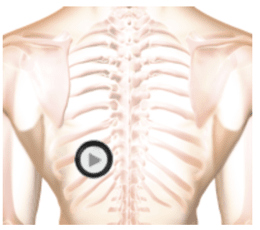

The auscultation location is indicated on the chest wall (torso) to show where the stethoscope was placed and the patient was seated